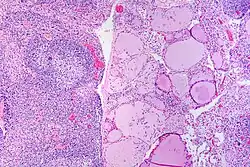

![]() | Tuberculous granuloma | Caseating granulomatous lesion with areas of amorphous granular eosinophilic necrotic debris known as caseation (on the right half) bordered by collections of epitheloid cells, Langhan giant cells and lymphocytes. | Category: Histopathology of tuberculous granuloma | Tuberculous granuloma |

![]() | Caseous necrosis | Caseating granulomatous lesion with areas of amorphous granular eosinophilic necrotic debris known as caseation (on the right half) bordered by collections of epitheloid cells, Langhan giant cells and lymphocytes. | Category: Histopathology of caseous necrosis | caseous necrosis |

![]() | Tuberculous lymphadenitis | Caseating granulomatous lesion with areas of amorphous granular eosinophilic necrotic debris known as caseation (on the right half) bordered by collections of epitheloid cells, Langhan giant cells and lymphocytes. | Category: Histopathology of tuberculous lymphadenitis | Tuberculous lymphadentis |